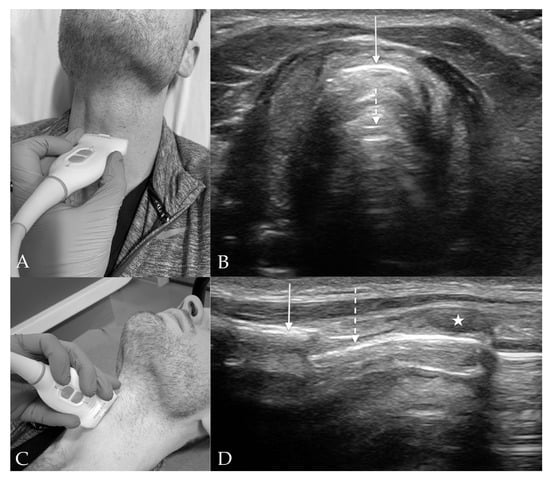

3. Probe Selection and Technique

4.3. Thyroid View

4.4. Cricothyroid View

4.5. Suprasternal View